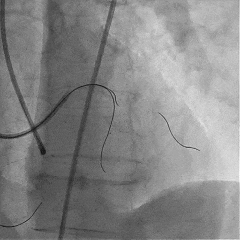

双腔微导管辅助下,导丝在逆向造影指引下成功通过LAD闭塞段,逆向造影显示导丝走行于LAD真腔内

交换工作导丝至LAD远端

预扩球囊依次扩张LAD近中段病变处,造影可见远端血管显影,导丝位于真腔。